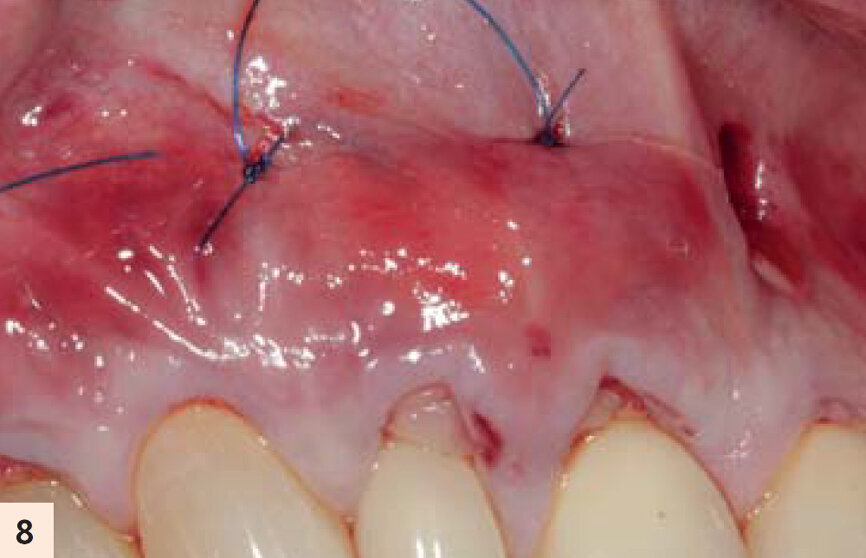

figure 8 : La suture périostée apicale en-dessous de la jonction muco-gingivale va « élever » le complexe A-PRF/lambeau en direction coronaire. La proximité intime entre les membranes d’A-PRF et les ligaments parodontaux permettra une libération lente des facteurs de croissance, favorisant ainsi la kératinisation.

Ces observations, corrélées avec l’expérience clinique des auteurs, les ont amené à conclure qu’il faut 3 ou 4 membranes par couple de dents, pour obtenir une fibropromotion cliniquement visible (Figs. 2–4).